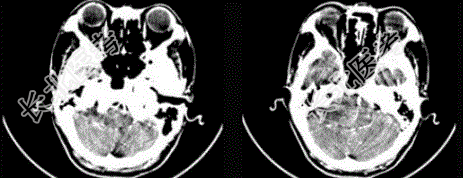

- 单项选择题女,45岁, 右耳听力下降半年余,CT检查如图, 最可能的诊断是